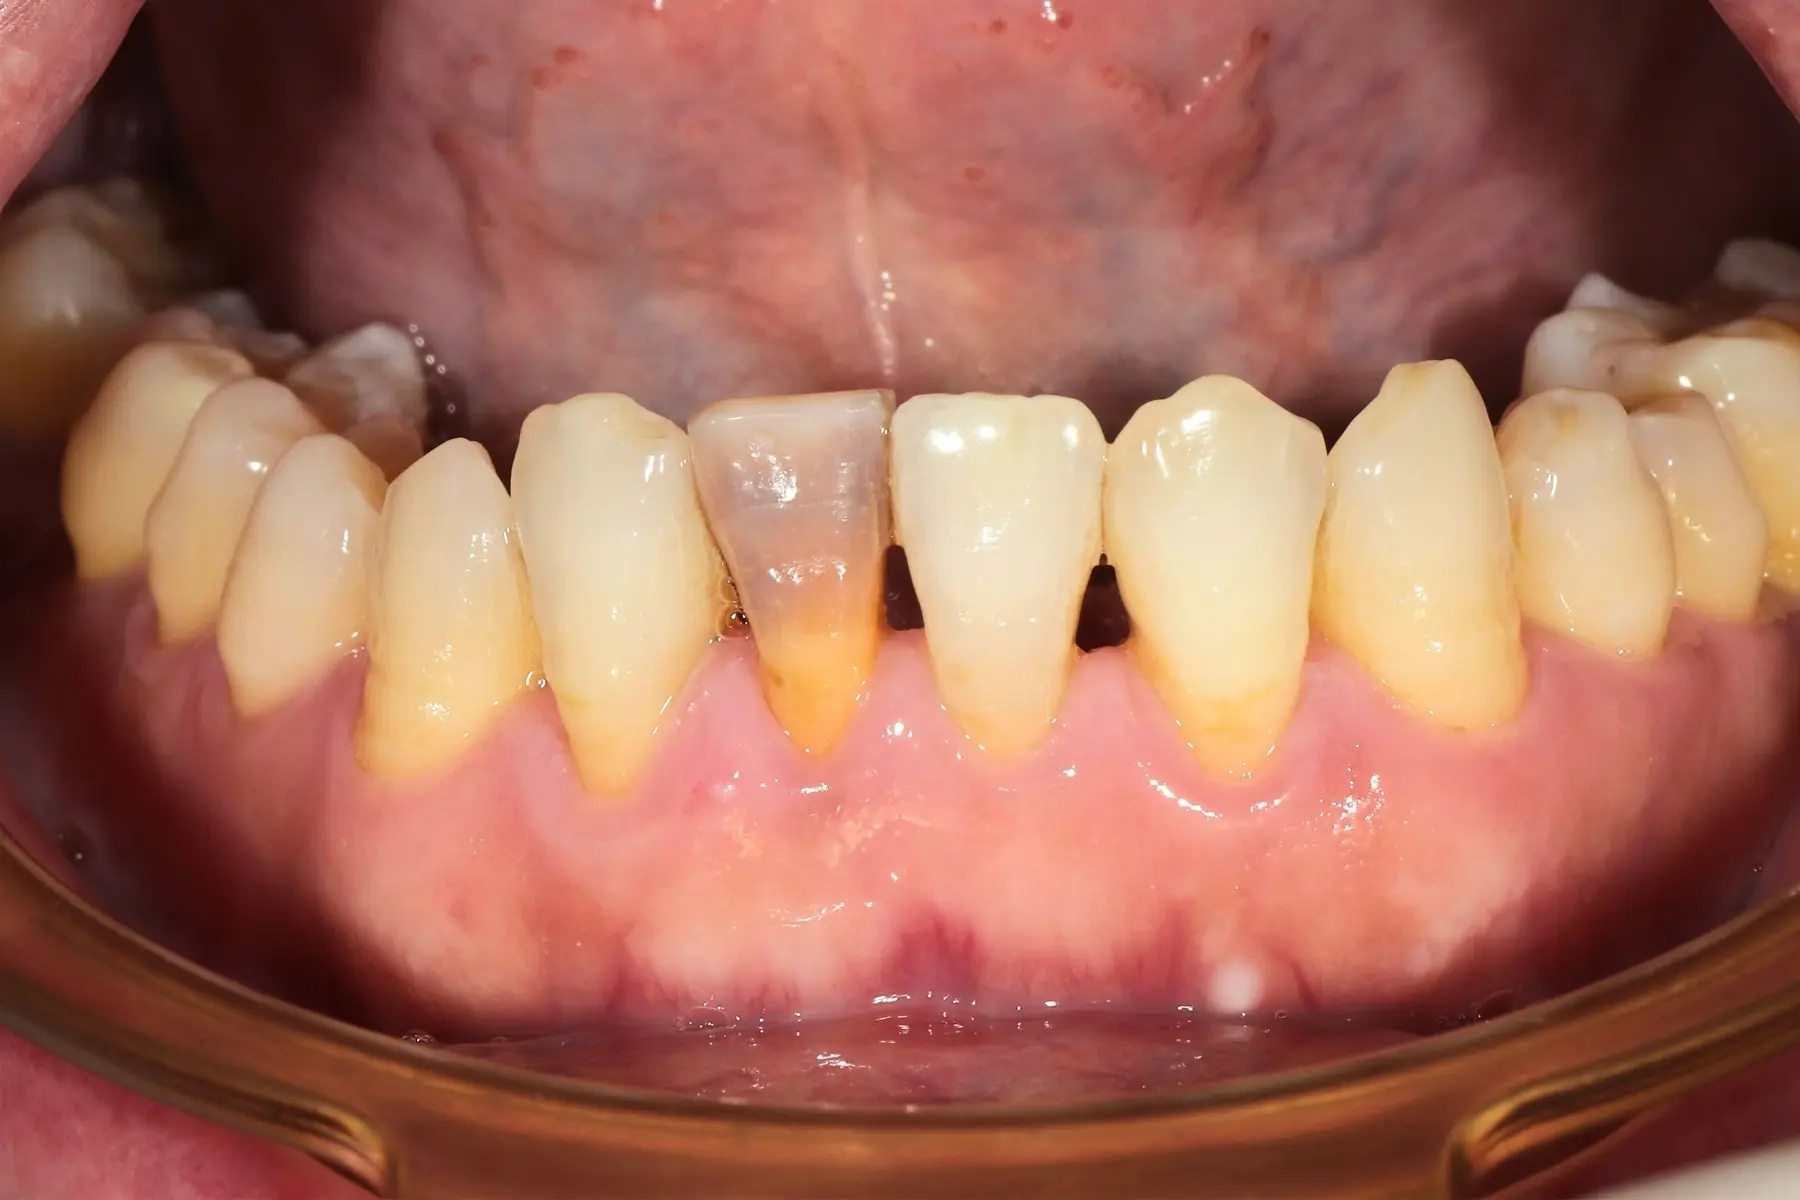

• 術前 42

術後 40

牙周治療

主治醫師

• 鍾國耀

治療時間

三次療程

主訴

右上前牙牙齦反覆腫脹化膿